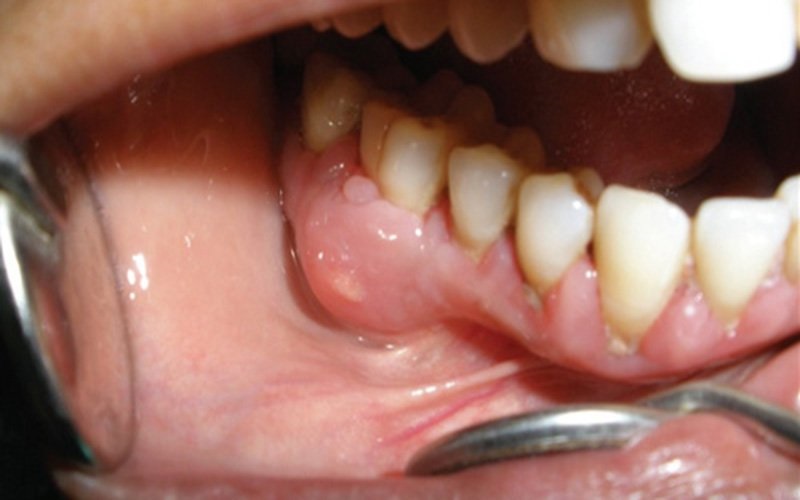

Viêm tủy, mất răng:

Sâu răng không được điều trị kịp thời sẽ tiếp tục lan sâu vào trung tâm răng, nơi có tủy răng (chứa dây thần kinh và mạch máu). Điều này dẫn đến viêm tủy, gây ra những cơn đau dữ dội, đau lan lên đầu, và đau buốt tự phát, đặc biệt là vào ban đêm.

Viêm tủy nếu không được điều trị có thể dẫn đến hoại tử tủy và nhiễm trùng lan xuống chóp chân răng, hình thành áp xe. Trong trường hợp nhiễm trùng nặng không thể cứu chữa, bác sĩ buộc phải nhổ răng để ngăn chặn nhiễm trùng lây lan, dẫn đến mất răng vĩnh viễn và ảnh hưởng đến xương hàm.

- Điều trị tủy: Nếu vi khuẩn đã xâm nhập và gây viêm hoặc hoại tử tủy răng, việc điều trị tủy là bắt buộc. Bác sĩ sẽ tiến hành làm sạch toàn bộ hệ thống ống tủy, loại bỏ mô tủy bị viêm nhiễm, sau đó trám bít kín hệ thống ống tủy.

- Nhổ răng: Đây là giải pháp cuối cùng và bất đắc dĩ. Nhổ răng chỉ áp dụng khi răng đã bị hỏng hoàn toàn, nhiễm trùng quá nặng, không thể phục hồi được bằng bất kỳ phương pháp nào và có nguy cơ ảnh hưởng đến các răng lân cận hoặc xương hàm.